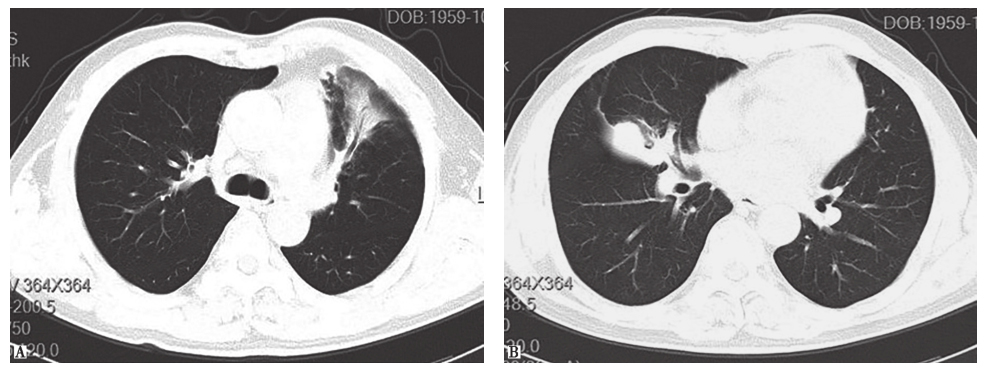

【影像学检查】

胸部CT见双肺多发片状密度增高影,伴多发空洞形成,并见局限性肺不张及实变。

经伏立康唑抗真菌治疗7天后,复查胸部CT见右肺中叶病灶有所吸收(图10)。

图10 治疗后复查胸部CT表现

确诊肺毛霉菌病后,用药改为两性霉素B联合氟胞嘧啶。治疗过程中复查肺部CT显示治疗效果较好,但病变吸收较缓慢,需较长疗程。治疗5个月后复查肺部CT发现病灶(左肺上叶及右肺中叶)明显吸收(图13),继续使用两性霉素B联合氟胞嘧啶治疗。

图13 抗真菌治疗5个月后复查胸部CT表现